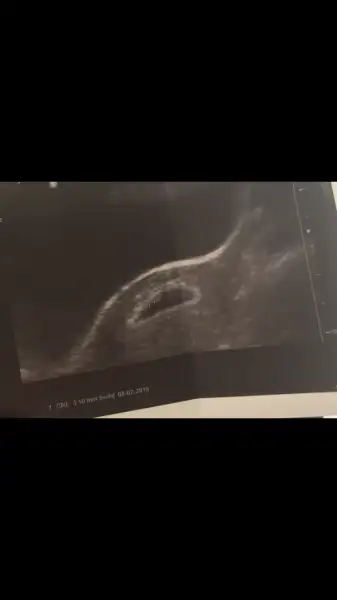

gözün aydın cnm darısı başımızaDoktora gittim sabahtan kesenin yanında az bi kanama var tedbir olsun diye Progestan verdi sabah akşam vajinalden alırsan daha iyi olur dedi.Güzel haberlerim de var çok şükür kalp atışını duyduk

Canım gözün aydın keseyi görmüşsün. kalp atışını gittiğimde doktor bana 0.65 cm dedi Bebeğe. Acaba neye göre 15 mm .Süper biz daha duyamadık. Haftaya kesin duyarız dedi. Gelişimi iyimis çünkü kese de 12mm olmus. 15 mm olduğunda galiba kalp atışı gorukiyormuş. Çok sevindim senin adına da. Benimde kesenin çevresinde kanamam varmış. Henüz dışarıya bir şey yansımadı tabi

Yok kuzum bebeğin değil kesenin boyutu 12mm bebeğin boyutunu sormadım. Karından baktığında kese gözüktü alttan bakınca bebeği de görebildi çünkü. Crl var ama elimde bakayım birazdanCanım gözün aydın keseyi görmüşsün. kalp atışını gittiğimde doktor bana 0.65 cm dedi Bebeğe. Acaba neye göre 15 mm .

Canım öncellikle hayırlı olsun icini karartma sakın internetede bakma bence. İlk hamileligimde forumlara yaxarken bu sorunla karsılasab ve düzelen cok arkadas gördüm:) Seninde öyle olur kalp atımınıda görmüssün bozma moraliniKızlar dün ikinci kontrolüme gittim doktor bi süre sessiz kaldı baya inceledi en korkutucu anlar sanırım. Aha dedim kötü bir haber geliyo. Sonra kesenin normale göre uzun ince olduğunu ama yırtık, kanama olmadığını bazen böyle durumların olabileceğini söyledi. Kalp atışı duyulmadı ama sonra gösterdi pıt pıt atma görüntüsü belirdi ekranda. 2 haftaya randevu verdi nasıl geçicek bilmiyorum çünkü araştırdığımda yine bozulmuş gebelik,düşük tehlikesi gibi bir sürü şey çıktı karşıma aranızda yaşayan var mı bu deneyimi?

içini ferah tut bebeğine güven canım internetten her gördüğün senin bebeğin için geçerli olmayabilir bi süre okuma boyle şeyleri 2 hafta sonra kalbini duyunca rahatlarsınKızlar dün ikinci kontrolüme gittim doktor bi süre sessiz kaldı baya inceledi en korkutucu anlar sanırım. Aha dedim kötü bir haber geliyo. Sonra kesenin normale göre uzun ince olduğunu ama yırtık, kanama olmadığını bazen böyle durumların olabileceğini söyledi. Kalp atışı duyulmadı ama sonra gösterdi pıt pıt atma görüntüsü belirdi ekranda. 2 haftaya randevu verdi nasıl geçicek bilmiyorum çünkü araştırdığımda yine bozulmuş gebelik,düşük tehlikesi gibi bir sürü şey çıktı karşıma aranızda yaşayan var mı bu deneyimi?

altran baktırmazsan görülmeye bilir. ama goruledebilir bebeğin gelişimine bağlı arkadaşım. Benim bebeğim. Şuanda 6 haftalık kalp atışı gözükmedi meselaBende haftaya keseyi görmeye gitcemm 6 hftam oluyor hataya görebilir miyim hem kalp hem kese doktorvtuttrdu alttan bakcaz die bn istemedim